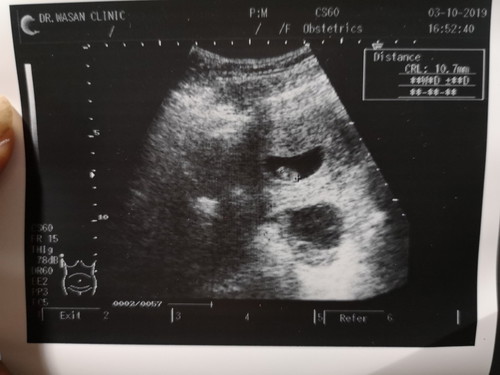

วันนี้ไปซาวด์ดูลูกน้อย ซึ่งเราแจ้งหมอไปว่าท้องได้ 9 weeks แล้ว... แต่คุณหมอบอกว่าขนาดของลูกน้อยเราไม่น่าถึง 9 weeks ขนาดของเด็กในฟิล์มแค่10.7mm.เองยังไงก็ไม่ถึง นั่นหมายความว่าแม่จำวันเป็นประจำเดือนผิดใช่มั้ยคะ??